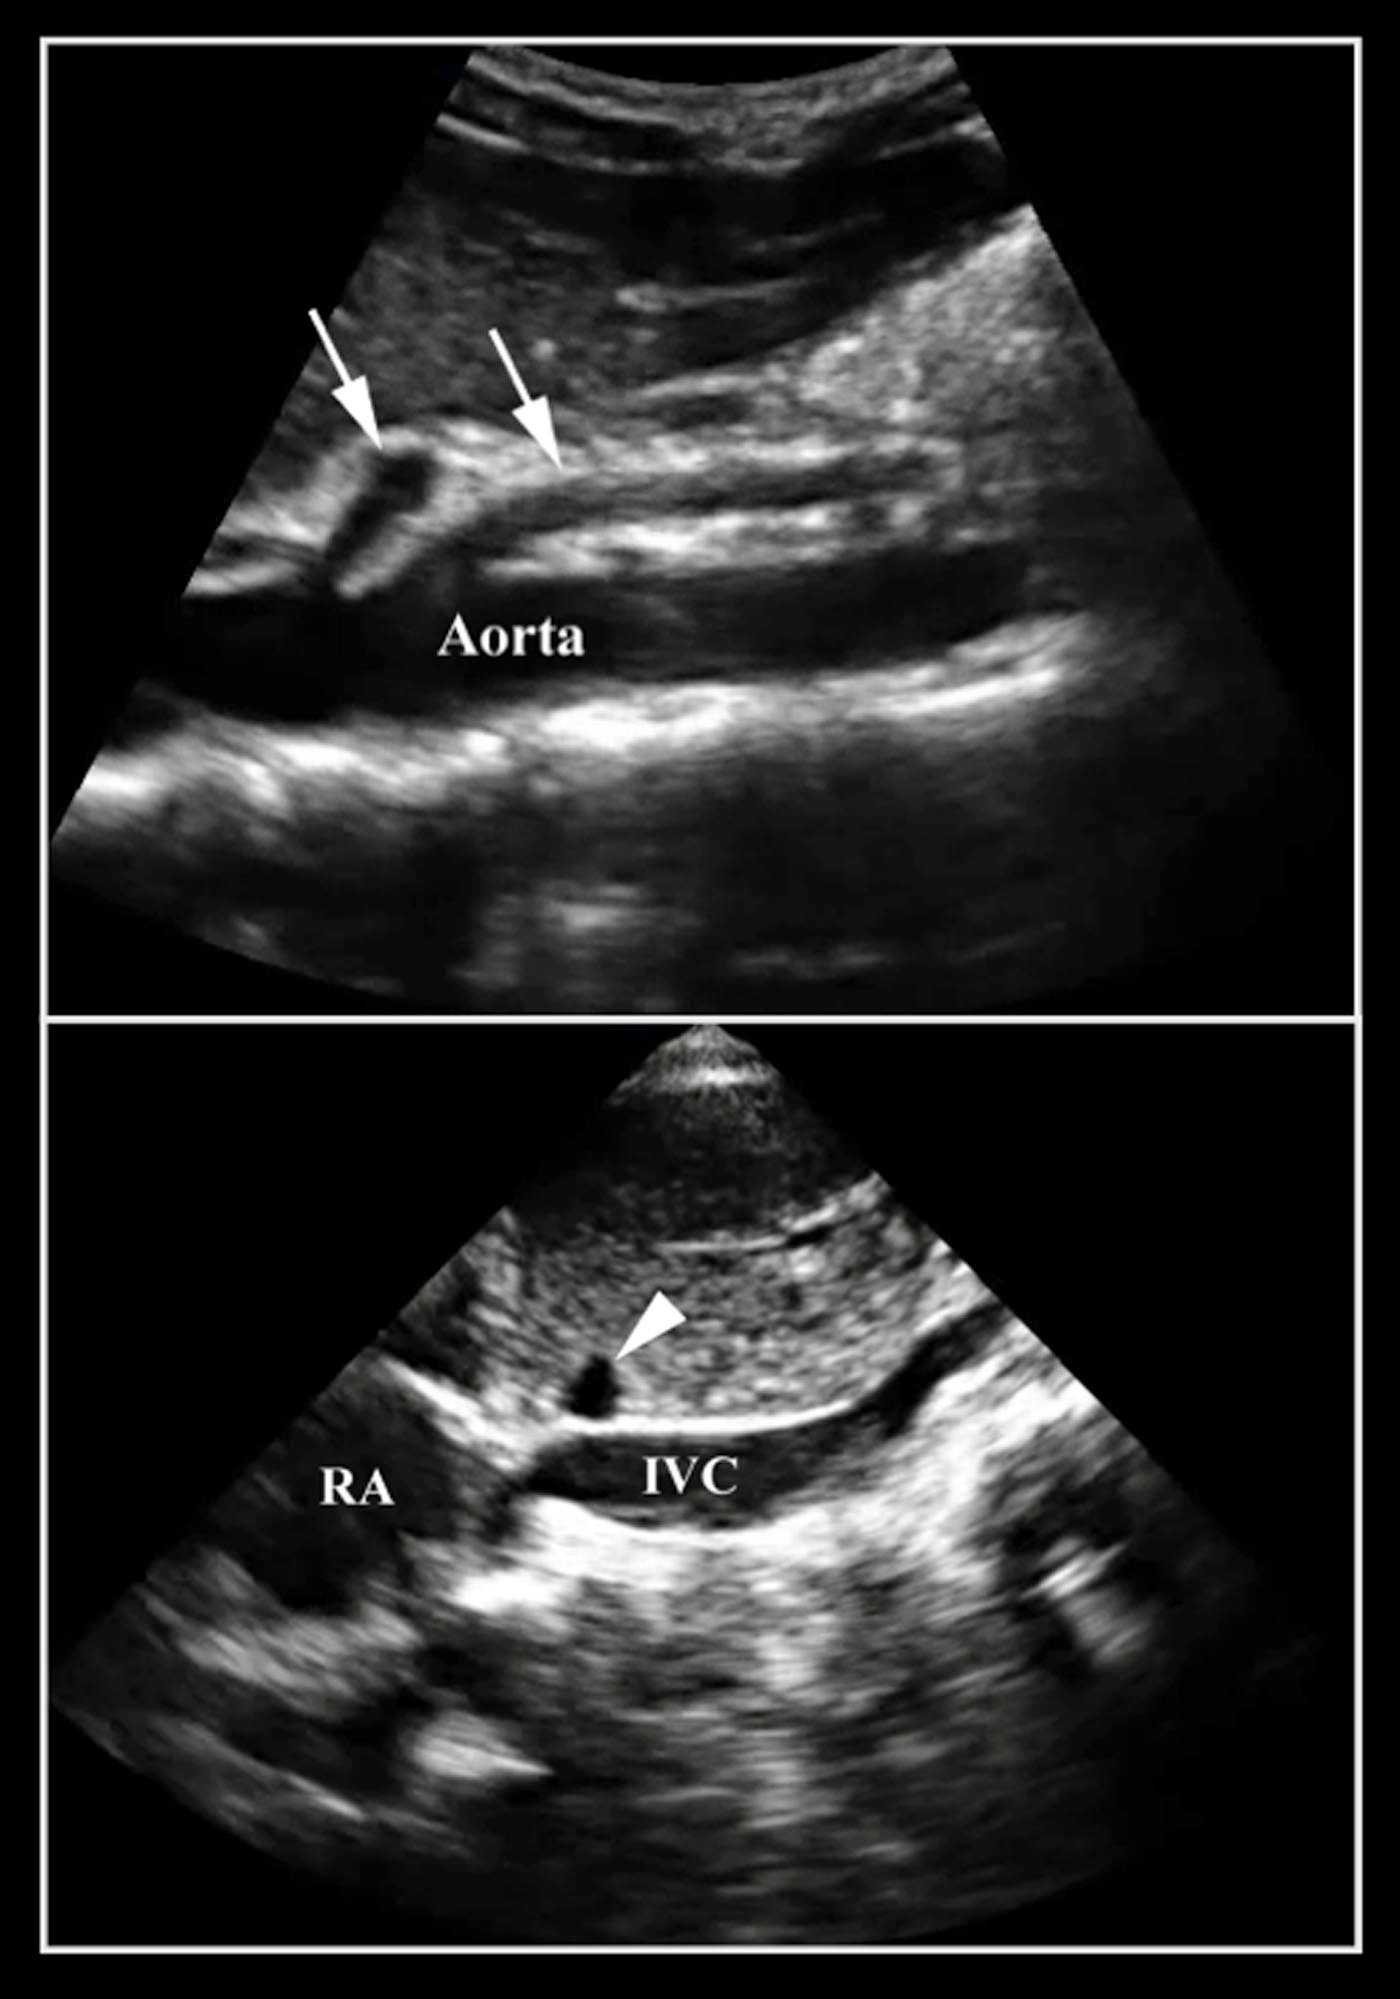

- Do not mistake the IVC for the aorta. It is important to identify the branches of the aorta. The IVC will run through the liver with the hepatic vein draining into it. You can also identify the IVC entering into the right atrium (Figure 9).

- Figure 10. Note the difference between the aorta and the IVC